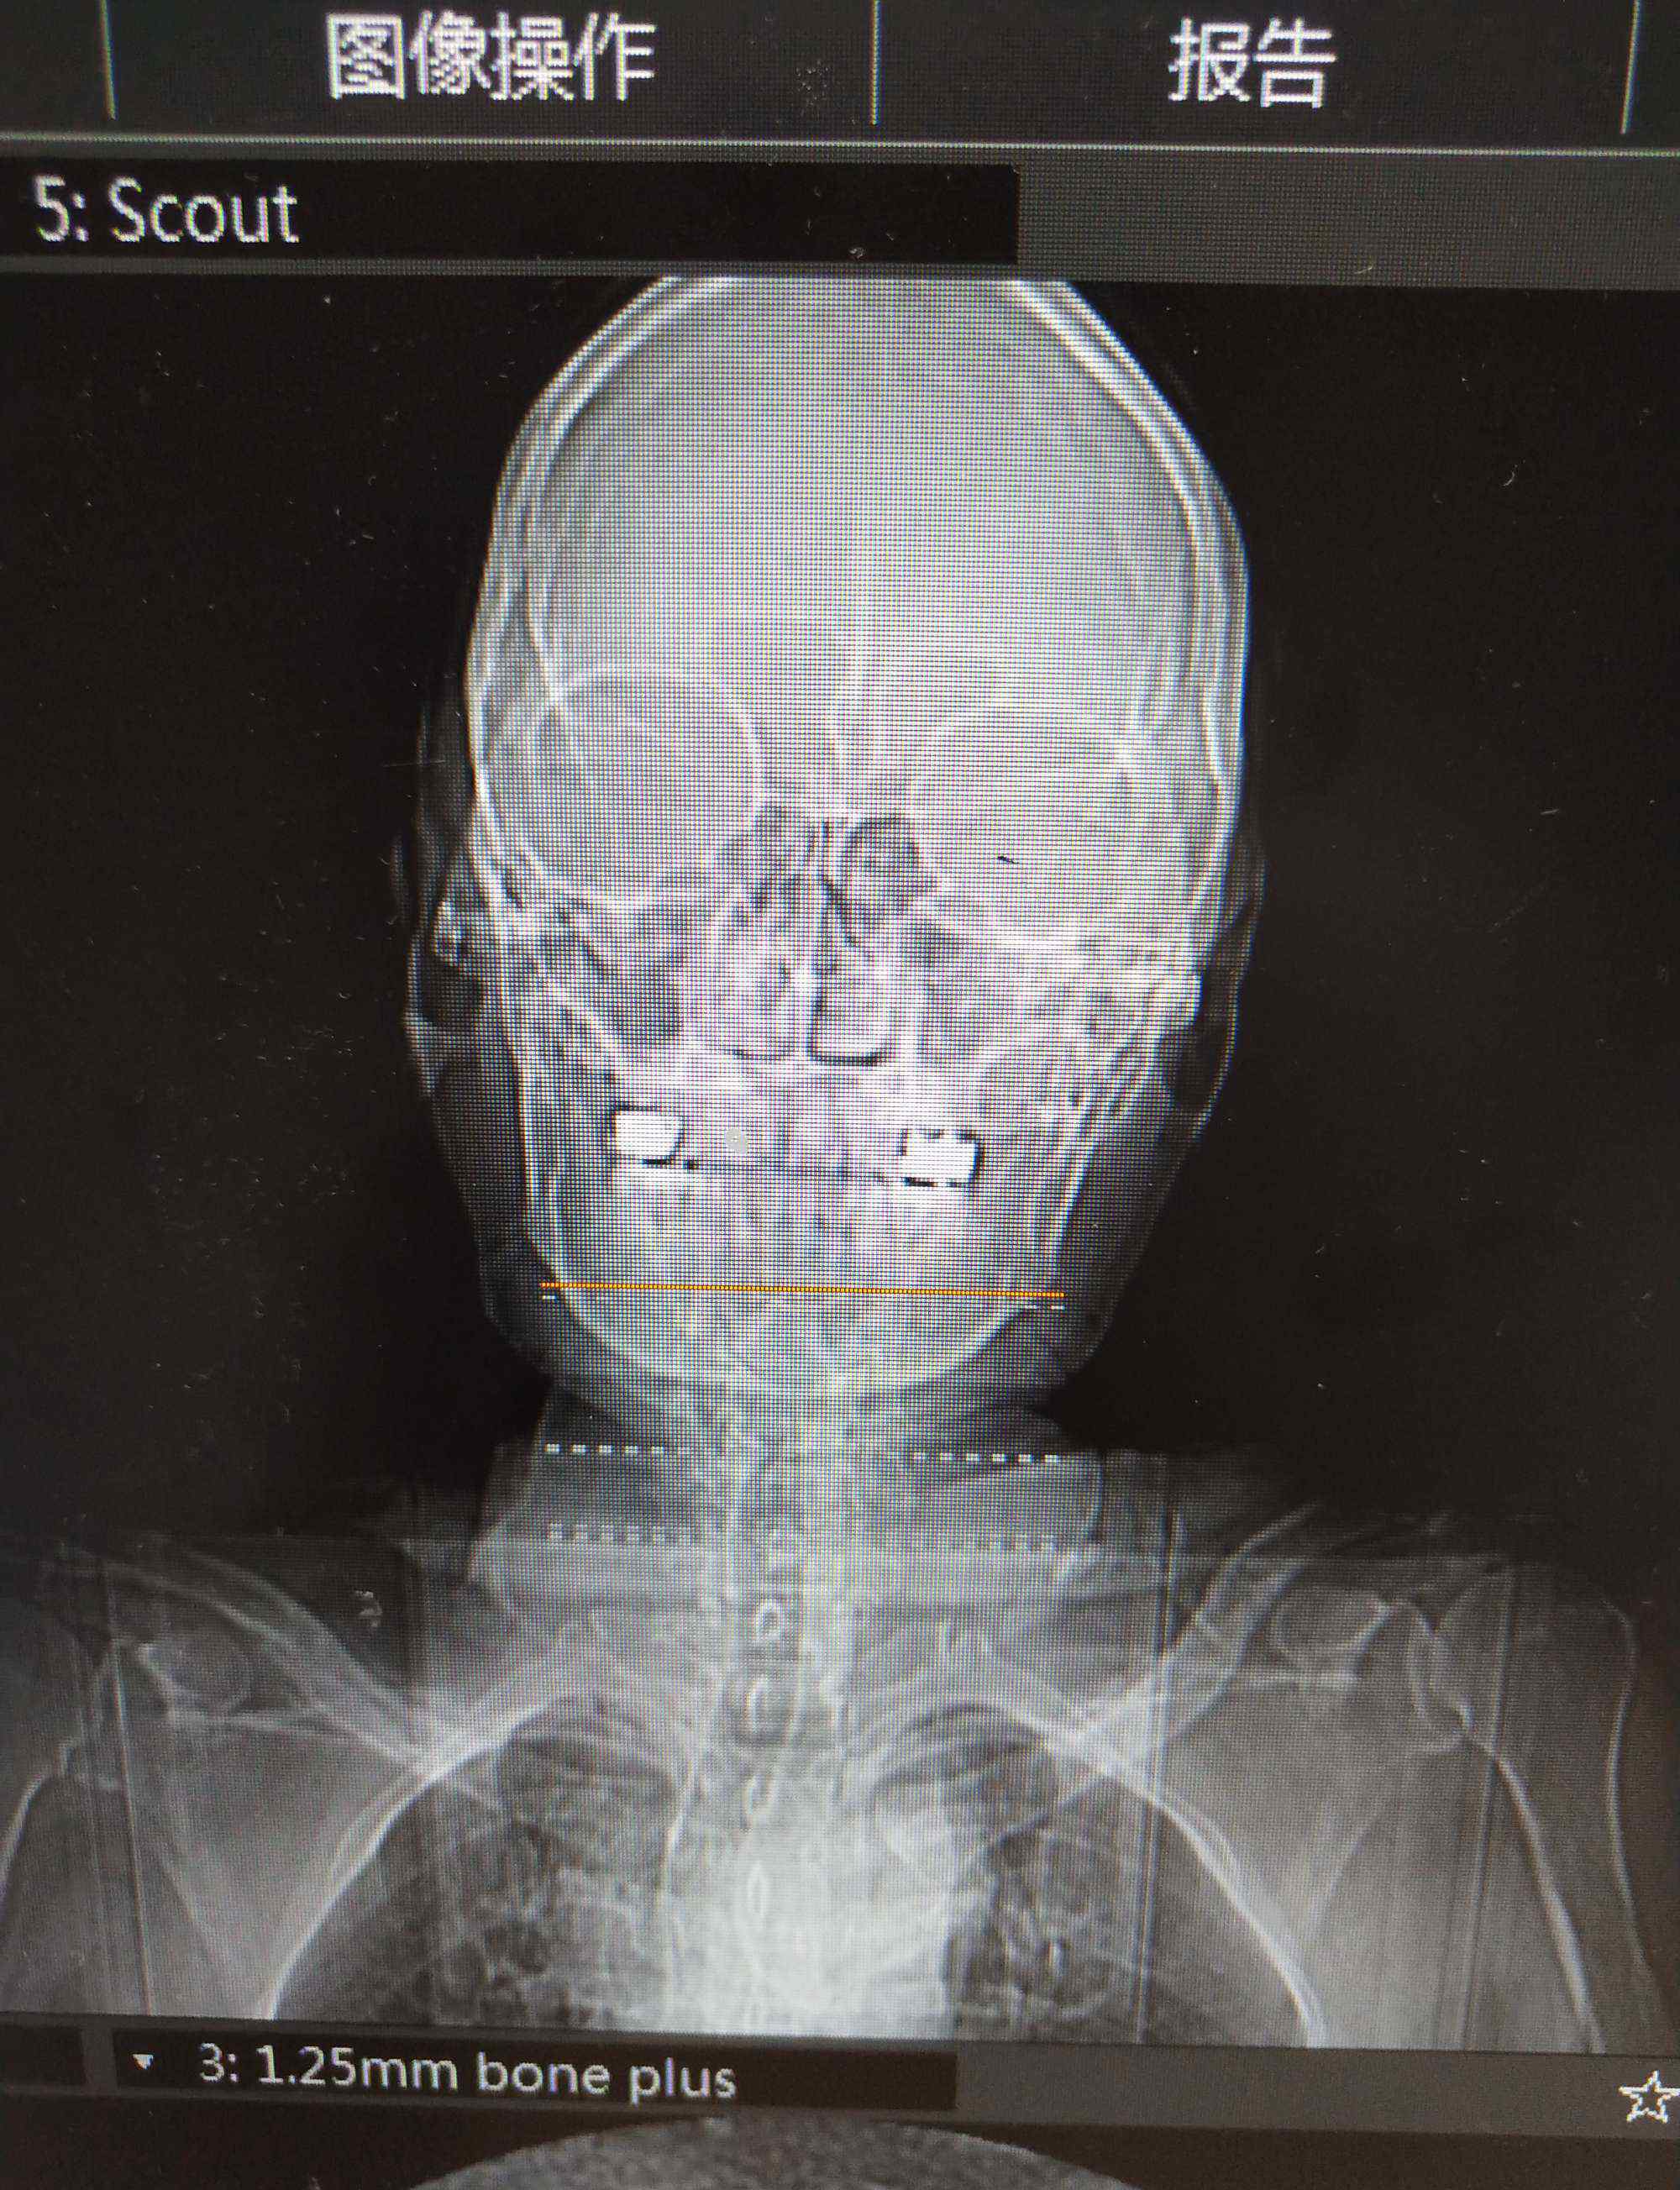

CT

MRI